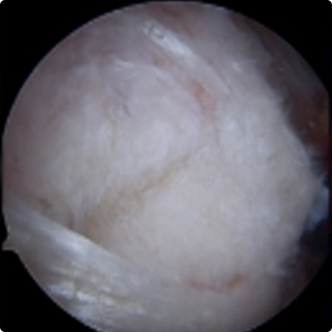

회전근개파열의 여러 모습들

기존의 삼각근을 절개하고 회전근개를 노출시켜서 수술하는 방법이 아닌 초소형 카메라인 관절내시경을 삼각근을 통과시켜 회전근개파열을 봉합합니다. 힘줄 주변의 근육 손상을 최소화시킬수 있기 때문에 수술 후 유착 반응이나 통증 반응이 감소하여 빠른 재활이 가능합니다.